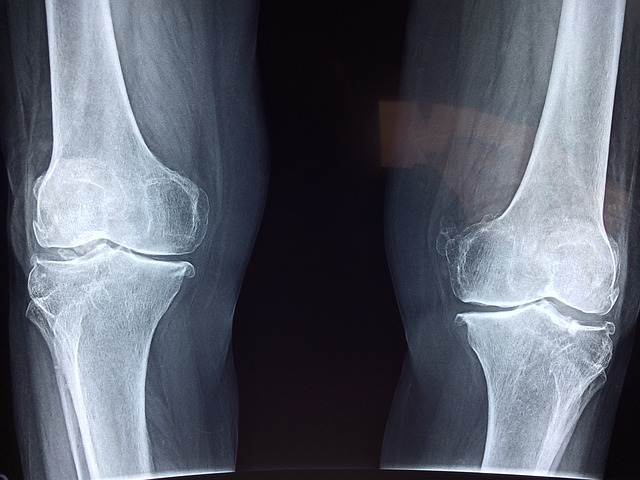

- 무릎 관절: 대퇴골과 경골을 연결하는 관절

무릎 관절

- 콘드로이틴: 연골 재생과 관절 기능 개선

- MSM: 관절 염증 감소와 통증 완화